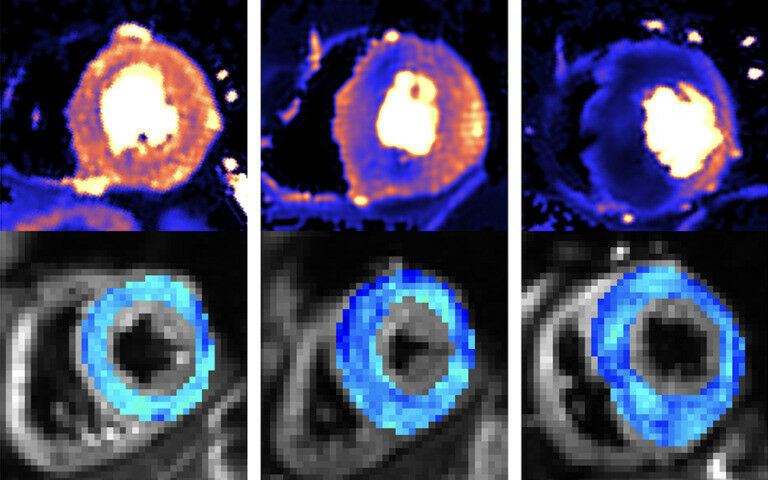

MRI images of the hearts of a healthy volunteer (left), individual with HCM gene but no symptoms (middle), patient with overt HCM (right). Top: quantitative perfusion images showing defects in heart muscle blood flow (dark blue), bottom: cardiac diffusio

MRI images of the hearts of a healthy volunteer ( left ), individual with HCM gene but no symptoms ( middle ), patient with overt HCM ( right ). Top: quantitative perfusion images showing defects in heart muscle blood flow ( dark blue ), bottom: cardiac diffusio Combining two types of heart scan techniques could help doctors to detect the deadly heart condition hypertrophic cardiomyopathy (HCM) before symptoms and signs on conventional tests appear, according to a new study led by UCL researchers. The research, funded by the British Heart Foundation and published in the journal Circulation , opens the prospect of treating the condition at the earliest stages. Being able to detect HCM earlier than ever before will also assist trials investigating gene therapies and drug treatments aimed at stopping the disease developing in those at risk. HCM is an inherited condition that affects around 1 in 500 people in the UK. It causes the muscular walls of the heart to become thicker than normal, affecting how well the heart can pump blood around the body. It is a leading cause of heart failure and sudden cardiac death.